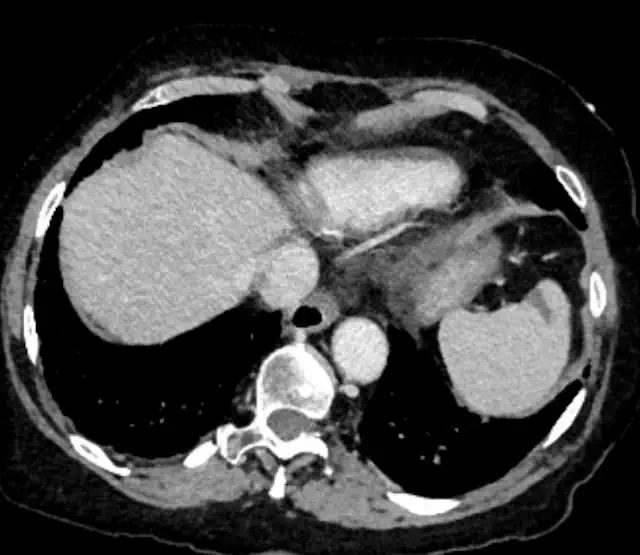

CT and MRI can also diagnose deep vein thrombosis. They are most useful for identifying findings in the abdomen and pelvis. However, they are sometimes used to assess the veins in the extremities, like in this example: